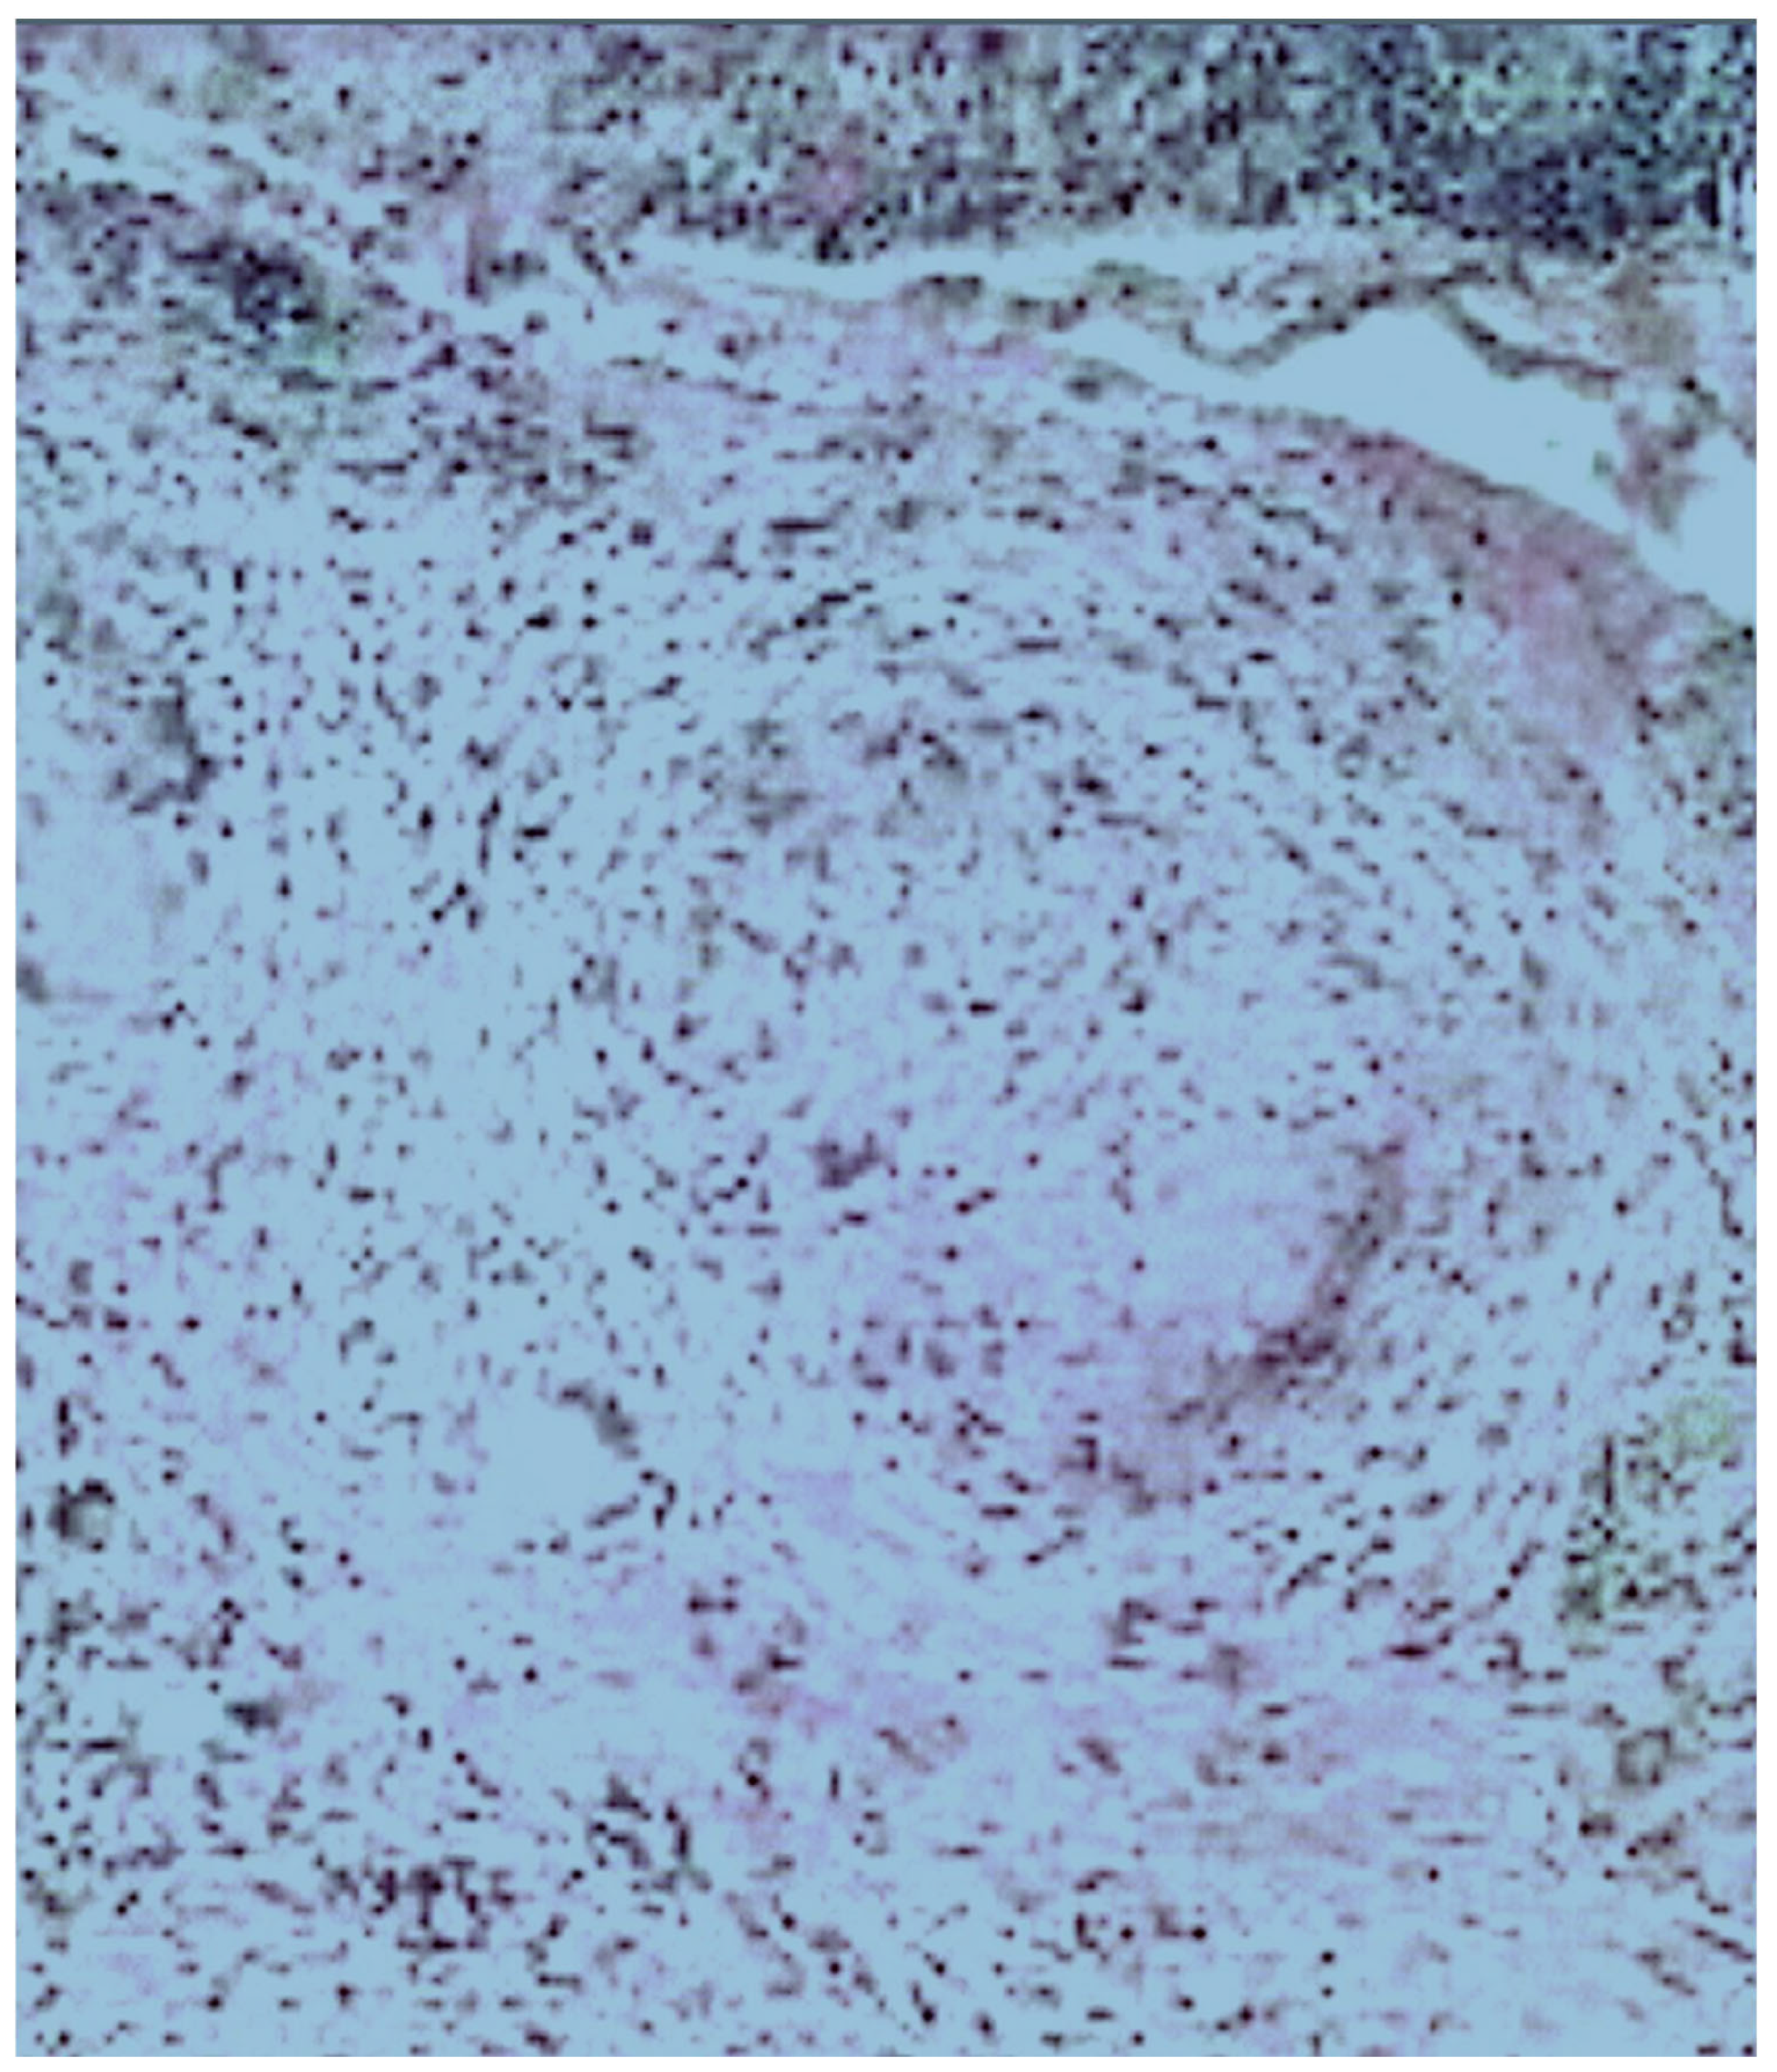

2. Case Presentation